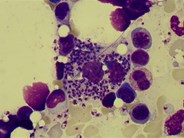

Visceral leishmaniasis involving the bone marrow

A 67-year-old white British man presented with a 2-month history of headache, fever, night sweats, and weight loss. Physical examination revealed splenomegaly. Laboratory tests showed a hemoglobin level of 111 g/L, white cell count of 1.5 × 109/L, neutrophil count of 0.4 × 109/L, and platelet count of 129 × 109/L. The man was HIV negative, and a blood film was nondiagnostic. Bone marrow aspirate showed (panel A) macrophages with intracellular forms of Leishmania amastigotes and (panel B) amastigote forms within a neutrophil. A culture of bone marrow in modified Novy-MacNeal-Nicolle media grew Leishmania promastigotes. Polymerase chain reaction with primers to amplify kinetoplast DNA minicircles on bone marrow was positive for Leishmania donovani. When asked retrospectively, he noted that he had delivered yachts in the Mediterranean over the last 5 years. His last trip to Portugal was 6 months before presentation. He had never traveled to the Indian subcontinent or central or east Africa where visceral leishmaniasis is endemic. The patient was treated with liposomal amphotericin B at a dose of 3 mg/kg/day from days 1 to 5 and day 10. His blood counts normalized, and his symptoms improved with regression of splenomegaly. Visceral leishmaniasis has infrequently been reported from southern Europe, northern Africa, and the Mediterranean according to the World Health Organization and should be considered in travelers regardless of ethnicity.